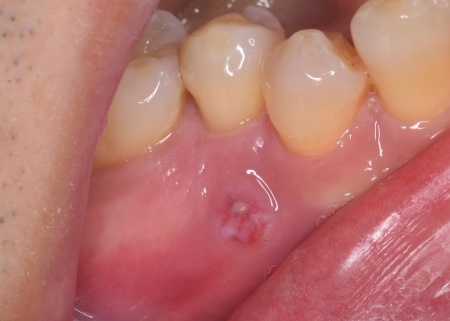

拝見したところ、左上の小臼歯が欠けていました。

レントゲンを撮り詳しく確認したところ、過去に根管治療が施されていたものの、根の中に薬がしっかりと詰められておらず治療が不十分な状態でした。そのため、根管から歯根を覆う歯根膜が細菌感染して炎症を起こす慢性歯根膜炎が生じています。

このまま放置すると細菌感染がさらに進行し、歯根周囲の骨が破壊されたり膿んだりして最終的に歯を失うおそれがあるため、早急な治療が必要と診断しました。